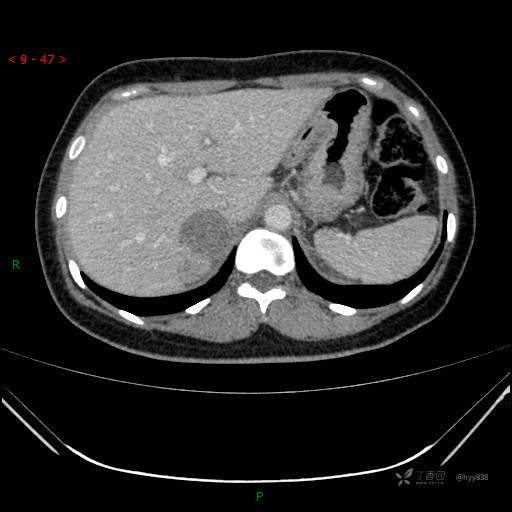

肾上腺CT平扫

动脉期

静脉期